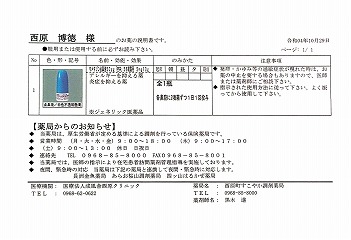

22.10.29 鼻炎薬吸引 モメタゾン点鼻液50μg 噴霧用 5mg10g 杏林 56噴霧用